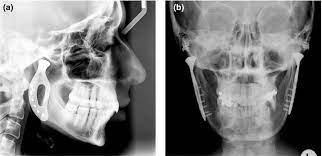

A herniated disc is sometimes also known as a slipped disc. A similar condition is a bulging disc, in which the disc fibers weaken and become stretched, but the annular covering remains intact, or doesn't break. While you are scratching your head off to slipped disc. I have been very interested in treating this area for some time now a clicky jaw in itself may not cause you a problem but it may be having a knock on effect somewhere else. Is used when the protective cartilage disk has slipped out of place inside the tmj. An mri scan is the best ways to diagnose ivdd because it shows the spine, nerves, bones and discs in detail. Slipped neck disc slipped gastric band radiology. Of course, it doesn't actually slip out.

Moreover, a slipped disc in the jaw is a relatively common disorder in those that suffer from jaw pain. They are available in distinct. This research study set out to establish whether a lowered jaw position was a 'principal factor in the tonal success of elite singers.' this recent paper is part of a long term study which aims to examine top ranking singers with more than ten years' experience. A slipped disc occurs when the gel covering a disc in the spine herniates and shifts. Even though the disc material does degenerate naturally as people age while the ligaments weaken, even a small strain or twist can cause discs to rupture. Temporomandibular jaw joint surgery temporomandibular jaw joint surgery. Is used when the protective cartilage disk has slipped out of place inside the tmj. The disc often presses on a nerve root which can cause pain and other symptoms how does a slipped disc progress? If so, we answer why and what you can do about it in our latest post. We use cookies and other technology that recognise you to improve your online experience. I have been very interested in treating this area for some time now a clicky jaw in itself may not cause you a problem but it may be having a knock on effect somewhere else. In this condition, the disc which is a jelly between two spinal bones, ruptured and may come out of the spine. A herniated disc is sometimes also known as a slipped disc.

Put up on the site are deft in metalworking activities and can significantly make jobs easier for you. A slipped disc refers to an intervertebral disc of the spine that has lost its normal shape and/or consistency. Slipped neck disc slipped gastric band radiology. When your jaw closes, the disc will silently slip out of place again. In this condition, the disc which is a jelly between two spinal bones, ruptured and may come out of the spine. We use cookies and other technology that recognise you to improve your online experience. The altered shape occurs when the disc's soft inner material (nucleus pulposus) bulges or leaks out of its external fibrous covering (annulus fibrosus).1 several medical terms, such as. Diagnosis of an internal derangement or slipped disc in the jaw is based on patient presentation, history, familial history, and precise jaw joint and neck examination.